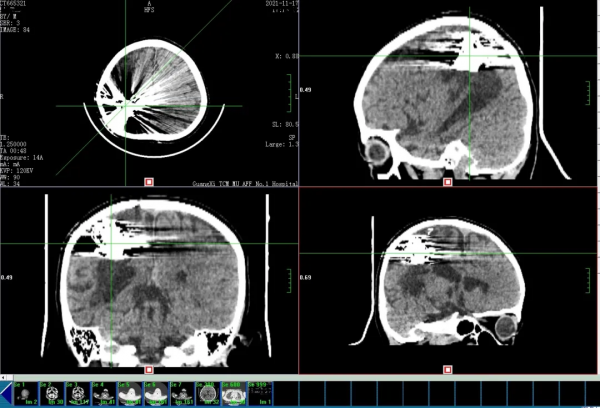

時機成熟,神經外科立即安排了全腦血管造影術——這是目前臨床診斷腦血管疾病最好的手段。術中清晰顯示了右側頂葉深部巨大的動靜脈畸形的每個細節,為醫師下一步治療提供了詳盡的情報。

集思廣益一直都是神經外科的優良傳統,科室主任組織全科醫師討論進行討論,經過積極討論,在反覆斟酌每一種手術方式的優勢和風險後,決定採用動靜脈畸形介入栓塞術——這是一種透過在血管內穿行的導管將醫用膠水(onix膠)打入畸形血管團,從而將畸形血管堵死的微創手術。難點主要在於準確的將導管送入指定的位置,以及恰如其分的將膠水灌滿整個畸形血管團,又不能溢位導致正常的血管被堵塞,需要極高的手術技巧及臨床經驗。

為了最大程度達到預期目標並最大限度降低風險,由黃建榮主任醫師和朱雲中副主任醫師這兩位廣西區內這一領域的“頂尖高手”聯手出戰。

經過緊張的手術和時間節點的精準把握,完美的封堵了病灶血管,這意味著導致患兒出血的“炸彈”被徹底的拆除了。